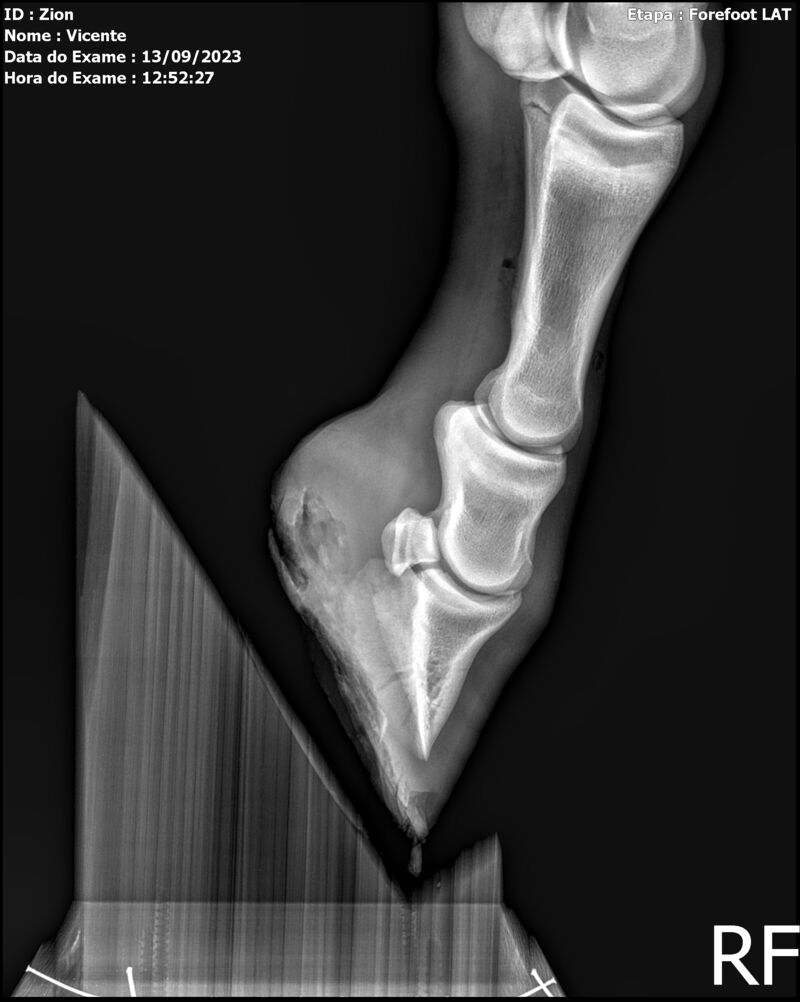

ZION ZC

Raça: BRASILEIRO DE HIPISMO

Sexo: MACHO - POTRO

Nascimento: 17/12/2022

Altura Aproximada: 1,51

Pel.: CASTANHO

Registro: EM AND

Vend.: VICENTE CONTE

Local : PORTO FELIZ/SP